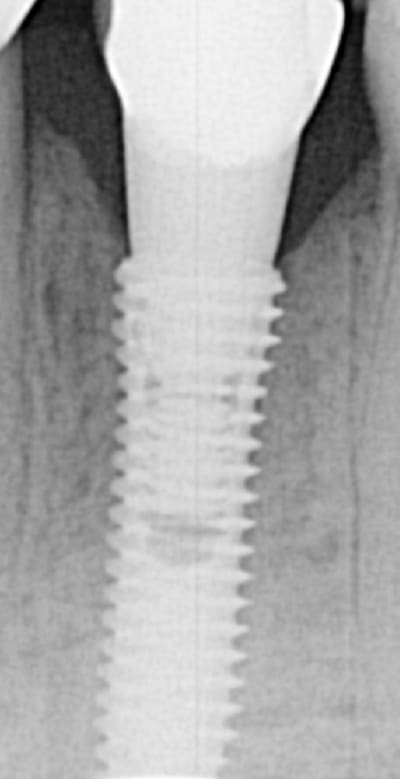

EII et Mise en vitrine immédiate, ici implant très enfoui, premier cliché à 3 mois post-op puis à un an (il faut préciser que le contrôle de plaque est plus que parfaitement réalisé par le patient).

(implant Dentium superline avec état de surface SLA)

> EII et Mise en vitrine immédiate, ici implant très enfoui, premier cliché à 3

> mois post-op puis à un an (il faut préciser que le contrôle de plaque est plus

> que parfaitement réalisé par le patient).

> (implant Dentium superline avec état de surface SLA)

Sympa comme résultat

'ai pensé à toi ce matin marcus

cas d'un axiom avec perte crestale et mise en charge en septembre voila l'évolution dans le temps la suite dans six mois